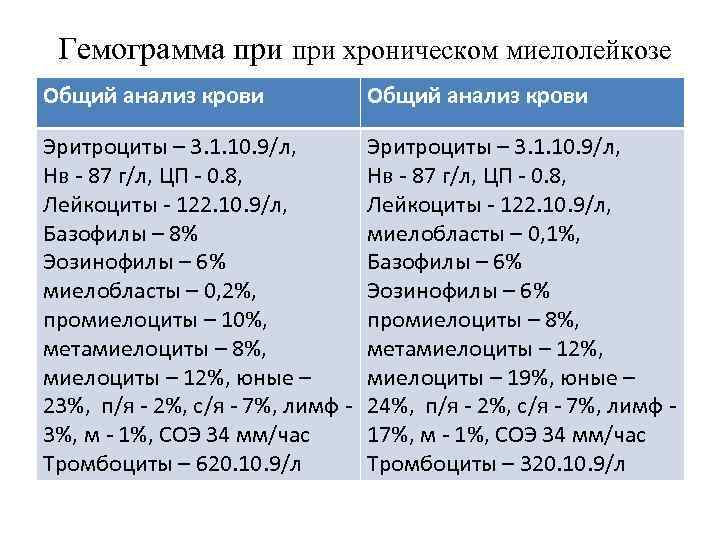

Гемограмма при хроническом миелолейкозе Общий анализ крови Эритроциты – 3. 1. 10. 9/л, Нв - 87 г/л, ЦП - 0. 8, Лейкоциты - 122. 10. 9/л, Базофилы – 8% Эозинофилы – 6% миелобласты – 0, 2%, промиелоциты – 10%, метамиелоциты – 8%, миелоциты – 12%, юные – 23%, п/я - 2%, с/я - 7%, лимф - 3%, м - 1%, СОЭ 34 мм/час Тромбоциты – 620. 10. 9/л Эритроциты – 3. 1. 10. 9/л, Нв - 87 г/л, ЦП - 0. 8, Лейкоциты - 122. 10. 9/л, миелобласты – 0, 1%, Базофилы – 6% Эозинофилы – 6% промиелоциты – 8%, метамиелоциты – 12%, миелоциты – 19%, юные – 24%, п/я - 2%, с/я - 7%, лимф - 17%, м - 1%, СОЭ 34 мм/час Тромбоциты – 320. 10. 9/л